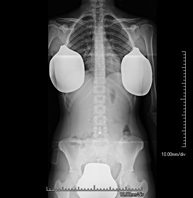

- Spinal teleradiology

This technique uses X-ray rendered imaging to examine the entire spinal column, especially assessing the presence of scoliosis and pelvic dysmetria.